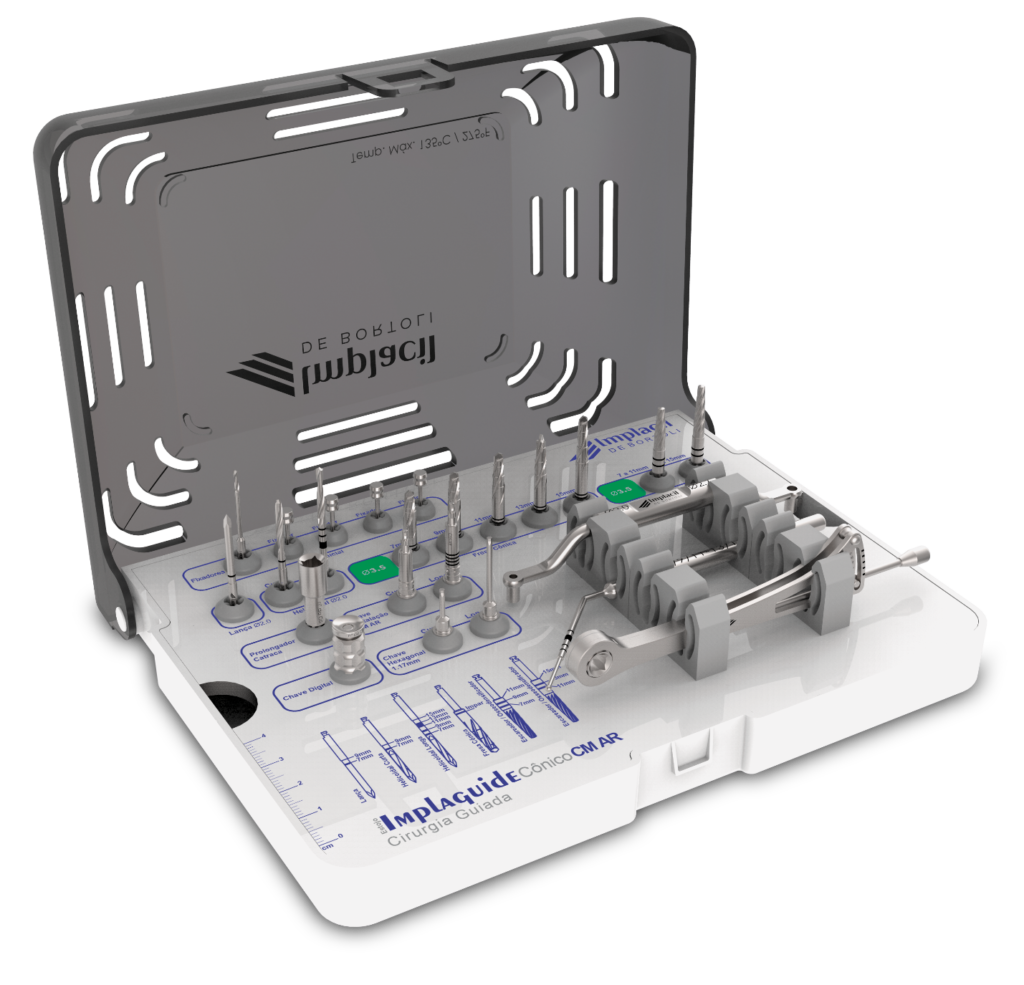

Através do programa Blue Sky (em parceria com a empresa Odontoplanning), foi feito planejamento guiado com 2 guias. O primeiro guia de recorte ósseo, tem como objetivo o recorte e aplainamento ósseo, deixando uma altura óssea mais uniforme entre a região posterior e anterior da mandíbula.